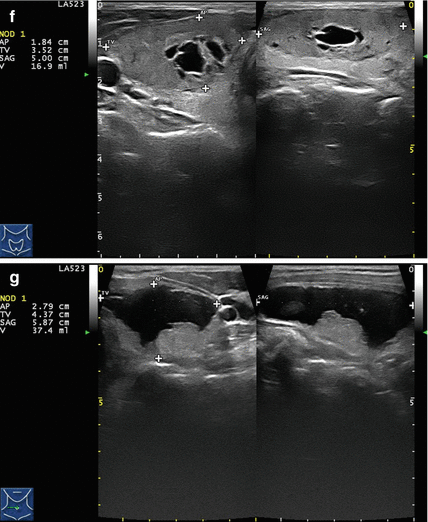

Facial pain info, trigeminal neuralgia is an inflammation of the trigeminal nerve causing extreme pain and muscle spasms in the face . . . . Glycerol injection provides immediate pain relief in 70% of patients [2] . About 50% of patients experience pain recurrence within 3 to 4 years . . . . In glycerol injection, alcohol (green) damages nerve fibers . . .